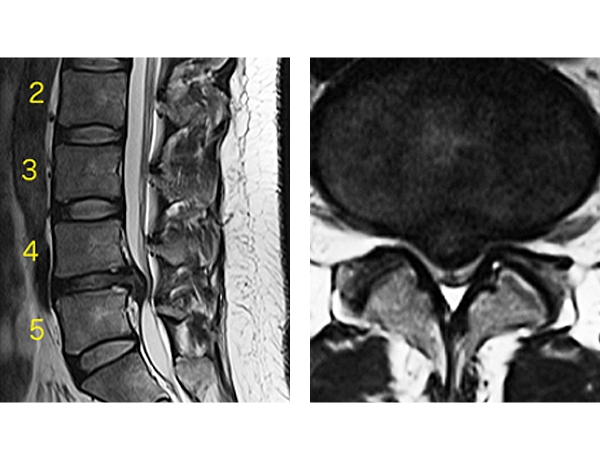

椎間板ヘルニア(腰椎)

35歳男性

第4、5腰椎間の正中部に変性髄核(椎間板)が大きく突出している